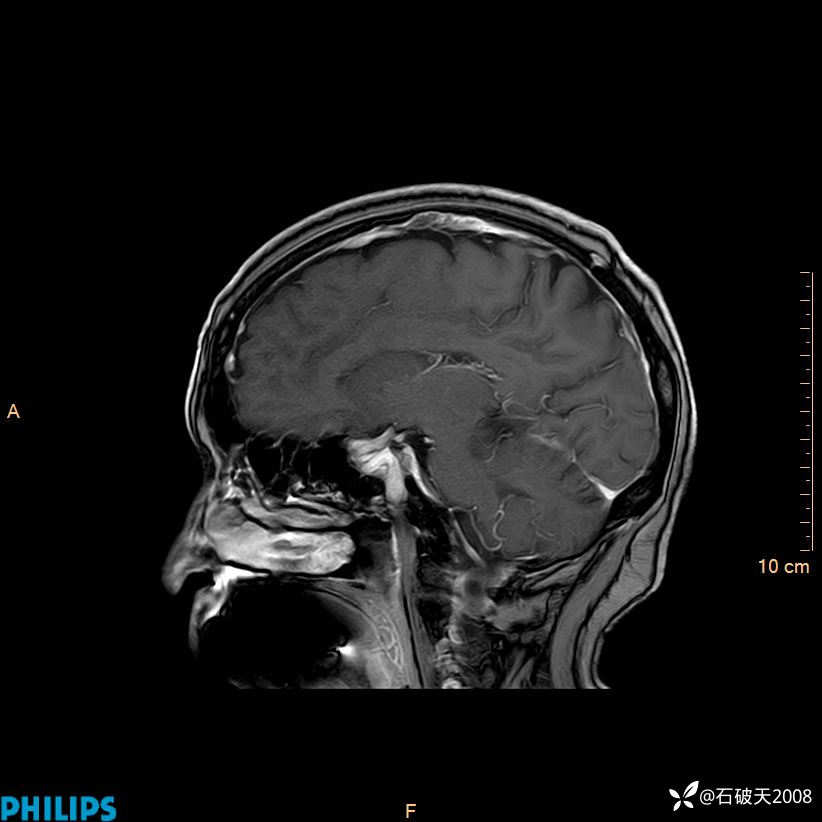

增强矢状位